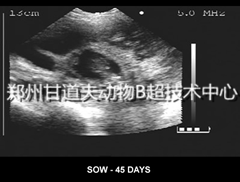

兽用B超检测怀孕母猪最早可在配种后21天进行,母猪配种是否准确有仔就来咨询甘道夫进口兽用B超厂家的猪用B超培训老师最佳时机在23-45天。母猪站立时操作比较方便,猪用B超测定位置在

其大腿内侧、最后乳头外侧腹壁,在探头涂上耦合剂,于猪头方向45度角紧贴在腹壁上探查。通过猪B超显示器,看到多个黑色

孕囊暗区或者胎儿骨骼影像即可确认怀孕,准确率可达100%。